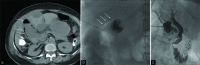

Objective: The objective of the study was to evaluate the safety and efficacy of percutaneous cholecystostomy (PC) in treating critically ill patients with emphysematous cholecystitis who were deemed poor surgical candidates.

Materials and methods: The Institutional Review Board exemption was obtained for this retrospective study. Patients with emphysematous cholecystitis who were deemed to be poor operative candidates by the treating surgeon and underwent PC placement between May 2008 and April 2017 at a single institution were identified through a medical records search. Demographics, laboratory values, imaging data, procedural technique, complications, hospitalization course, clinical outcome, and survival data were obtained.

Results: Ten consecutive patients were included, with a mean age of 75.0 ± 12.2 years, including six men and four women. The most common comorbidity was diabetes (60%, 6/10) followed by hypertension (40%, 4/10). Intraluminal or intramural gas as well as gallbladder wall thickening were noted in all patients. Procedure technical success rate was 100%. There was a complete resolution of symptoms in 90% (9/10) of patients at a mean of 2.9 ± 1.4 days post-procedure. Thirty-day survival rate was 90% (9/10); one patient died on the 6th post- procedure day from sepsis. Two more deaths occurred within a year after PC from unrelated causes. About 50% (5/10) of patients underwent elective cholecystectomy at a median interval of 69 days post-procedure. In 40% (4/10) of patients, cholecystostomy was the definitive treatment, with tube removal at a median of 140 days post- procedure.

Conclusion: PC appears to be a safe and generally effective alternative management option in patients with emphysematous cholecystitis that is considered very high risk for surgery.